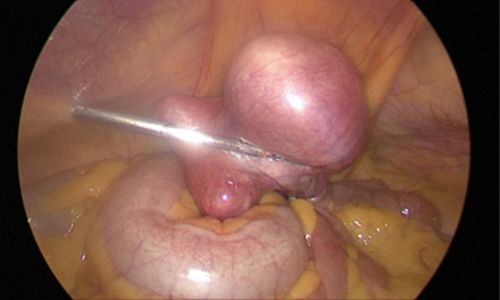

Photo showing a large fibroid in the fundus and body of the uterus:

During surgery, no incisions were made on the abdominal wall. The procedure was performed through the natural birth passage using a hysteroscope, which allowed direct visualisation of the uterine cavity. The fibroid was identified & removed using an energy source.